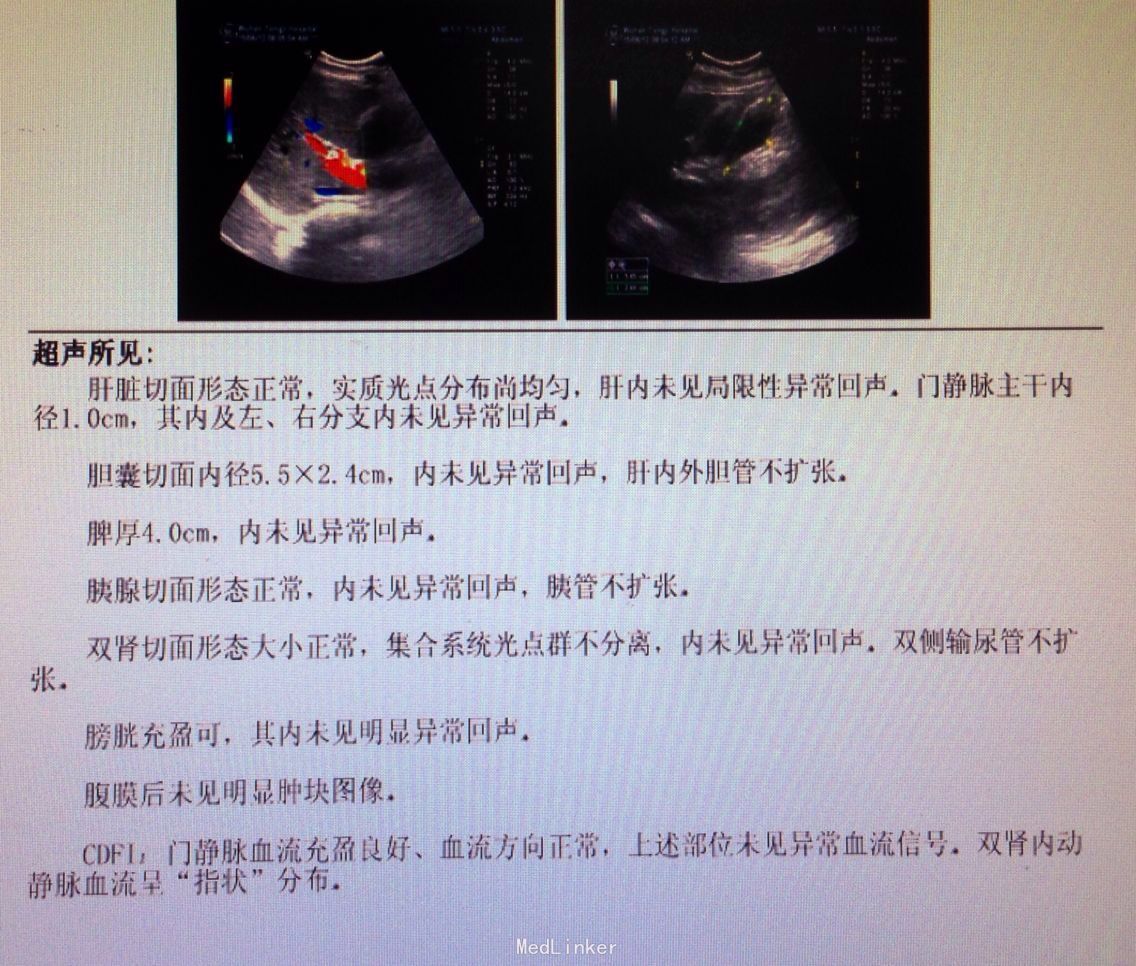

卵巢扭转的诊断主要 dựa vào 临床症状和体格检查。妇科医生可能会进行以下检查:- 详细询问病史和症状

- 妇科检查

- 超声检查

- 计算机断层扫描 (CT) 或磁共振成像 (MRI)